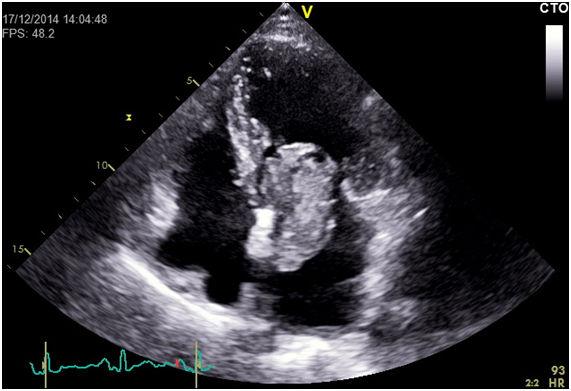

We report a case of a 57-year-old female, with previous history of smoking, hyperlipidaemia and history of ischemic stroke without residual deficits. She was ordered a transthoracic echocardiogram (ETT) to rule out cardiac embolism which revealed an echogenic left atrial mass of huge dimensions (5.8x2.8cm) connected by a small pedicle to the interatrial septum and prolapsing into the left ventricle in diastole causing transmitral flow obstruction (Figure 1) (Figure 2). Doppler revealed a mean pressure gradient between left atrium and ventricle of 9.71mmHg (Figure 3). Transthoracic 3D echocardiography allowed a better characterization of the mass and its attachment to the interatrial septum (Figure 4).

Figure 1 Ecocardiographic 4-chamber view showing giant left atrial myxoma prolapsing into left ventricular in diastole.

Figure 2 Echocardiographic 4-chamber view with colour doppler showing turbulent flow caused by transmistral flow obstruction by the giant left atrial myxoma.